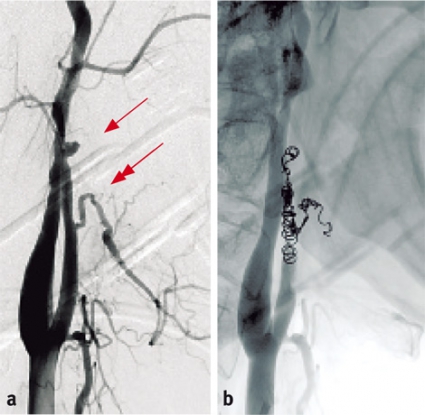

Angiografi av arteria carotis communis med beredskap till embolisering genomfördes. Undersökningen påvisade ett pseudoaneurysm lokaliserat proximalt på den artärstam utgående från höger arteria carotis externa som här utgör gemensamt ursprung för arteria facialis och arteria lingualis (Figur 1 a).

En mikrokateter lades in genom den befintliga angiografikatetern i höger arteria carotis communis och navigerades upp till pseudoaneurysmet, som ockluderades med platinaspiraler (Figur 1 b, 1 c).